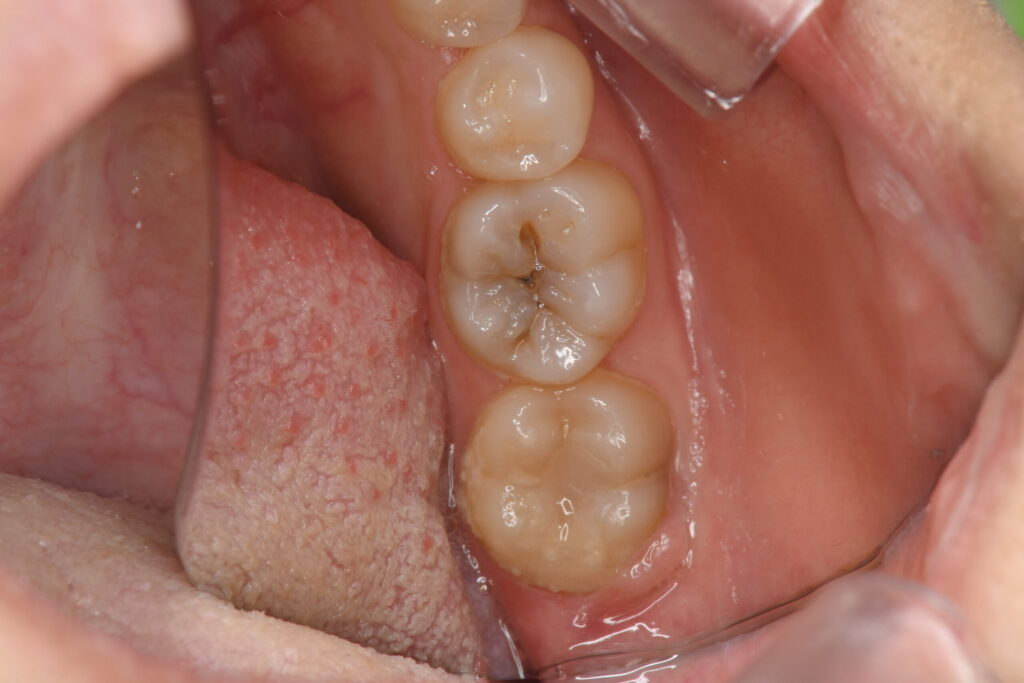

| 虫歯のダイレクトボンディング治療(20代女性) |

| 虫歯をダイレクトボンディングの技法を用いて治療した |